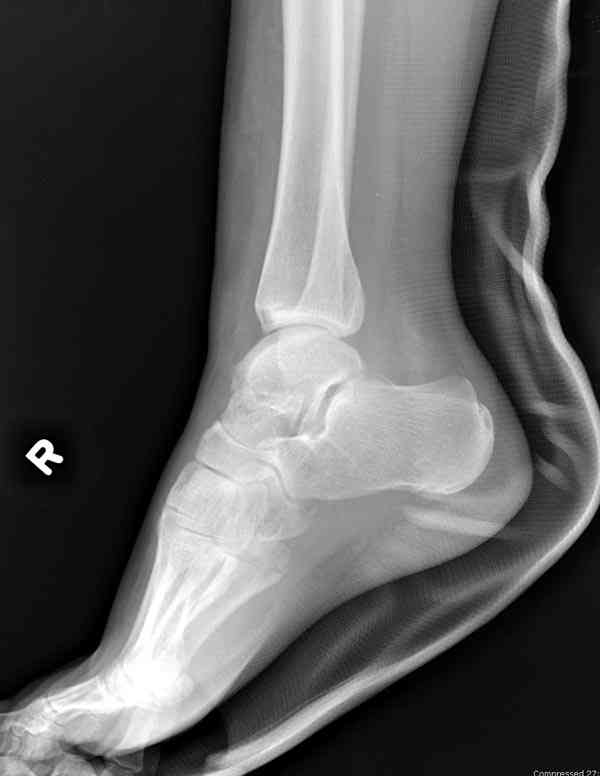

Случай с множественным оскольчатым переломом тарана оперированный из двойного доступа.

Через 8 мес.: